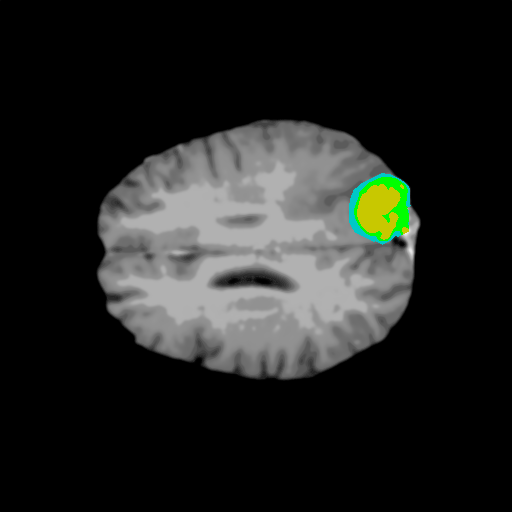

Extensive experiments have been performed in the current setup, and experimental outcomes are reported with the demonstration of numerical and statistical analyses using the proposed QFS-Net, QIS-Net [39], convolutional U-Net [18] and Residual U-Net (URes-Net) architectures [20]. The human expert segmented skull-tripped contrast enhanced DSC brain MR input image slices of size and ROIs are provided in Figure 5 as samples. The demonstration of QFS-Net segmented images followed by the essential post-processed outcome on the slice no. for class level with four distinct activation schemes () are shown in Figure 6. It is evident from the experimental data provided in Table LABEL:tab1 that the proposed QFS-Net performs optimally for the -connected quantum fuzzy pixel information heterogeneity assisted activation () with and gray scale set in comparison with other thresholding schemes and gray scale sets under the four evaluation parameters () [44]. The segmented tumors obtained using the proposed self-supervised procedure under class transition levels with four different thresholding schemes , , and are demonstrated in Figures 7- 8 for the class boundary sets and [39], respectively. The segmented images using the remaining two class boundary sets ( and ) [39] are provided in the supplementary materials section. The segmented ROIs describing the whole tumor region after the masking procedure using QIS-Net, U-Net and URes-Net are also reported in Figure 9.